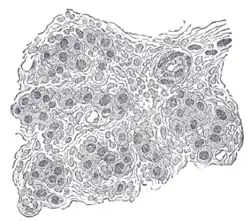

![]() Section of part of human carotid body. Highly magnified. Numerous blood vessels are seen in section among the cells. | |

The carotid body is a small cluster of chemoreceptor cells and supporting sustentacular cells situated at bifurcation of each common carotid artery in its adventitia.[1][2]

The carotid body is made up of two types of cells, called glomus cells: glomus type I cells are peripheral chemoreceptors, and glomus type II cells are sustentacular supportive cells.